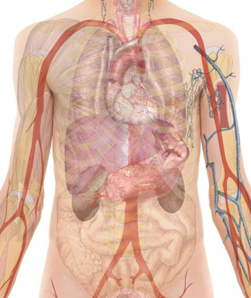

Cette unité apporte les bases nécessaires à la compréhension des grands systèmes du corps humain. Les enseignements portent sur les cellules, les tissus, les organes, la physiologie des systèmes et leur régulation. Ces cours sont dispensés à tou-tes les étudiant-es en sciences biomédicales, médecine humaine et médecine dentaire confondu-es.

Cette unité apporte les bases nécessaires à la compréhension des grands systèmes du corps humain. Les enseignements portent sur les cellules, les tissus, les organes, la physiologie des systèmes et leur régulation. Ces cours sont dispensés à tou-tes les étudiant-es en sciences biomédicales, médecine humaine et médecine dentaire confondu-es.

- Les bases de l'anatomie